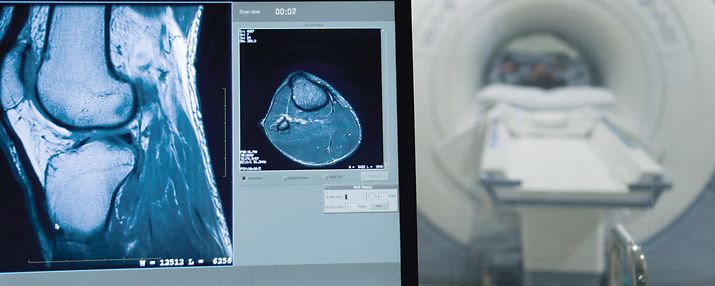

Dies ist natürlich nur ein kleiner Baustein zu mehr Nachhaltigkeit. Der Ressourcen- und Energieverbrauch im Gesundheitswesen ist enorm. Der CO2-Ausstoß ist größer als der des gesamten Flugverkehrs! Ein Gutachten im Auftrag der Deutschen Krankenhausgesellschaft hat die klima- und energierelevanten Daten der Krankenhäuser ausgewertet und sieht besonders im Bereich der Energie- und Stromversorgung ein großes Einspar-Potential. Insbesondere Operationssäle und radiologische Großgeräte wie MRT oder CT brauchen Lüftung, Kühlung, Heizung und vor allem viel Strom. Einsparungen im Bereich der Energie haben also oberste Priorität - damit werden nicht nur weniger Treibhausgase erzeugt, sondern es reduzieren sich auch die Kosten.

In diesem Jahr haben wir mit Energiemessungen von radiologischen Großgeräten begonnen. Aus den Energiemessungen erhoffen wir uns konkrete Hinweise darauf, in welchen Bereichen wir Energie einsparen können, sei es über das Nutzungsverhalten oder Energiesparoptionen der medizinischen Geräte. Als nächstes werden wir bei der Beschaffung von Neugeräten Kriterien wie Energieverbrauch, Reparaturmöglichkeit und Lebensdauerkosten mit einbeziehen.

Neben diesen übergeordneten Vorgaben für die Krankenhäuser haben die einzelnen Fachrichtungen natürlich spezifische Schwerpunkte, für die sie sich besonders verantwortlich sehen. Beispielsweise hat die Anästhesie einen hohen CO2-Fußabdruck aufgrund der verwendeten Narkosegase, die Allgemeinmedizin kümmert sich besonders um das Thema Hitzeschutz und die Radiologie hat durch die Großgeräte wie CT und MRT einen sehr hohen Energieversbrauch. Auch die Apothekerinnen und Apotheker sind mit im Boot, wenn es um das Thema Klimawandel und Gesundheit geht, wie kürzlich bei einer sehr informativen Fortbildungs-Veranstaltung von der Ärzte- und Apothekerkammer Sachsen-Anhalt gezeigt wurde.